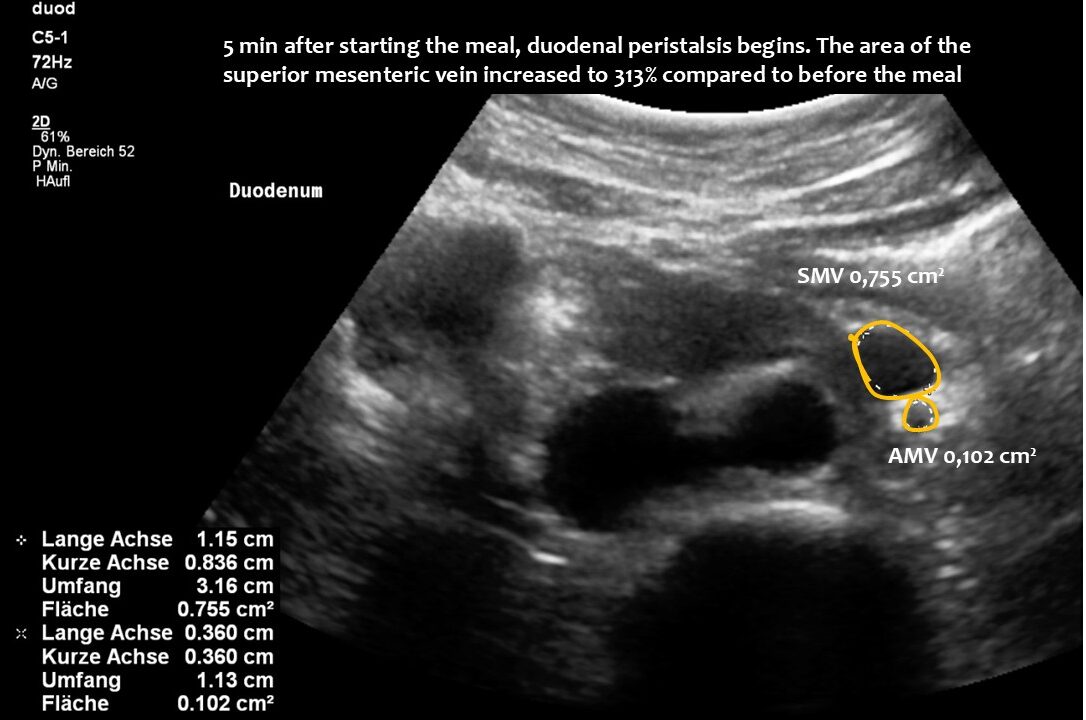

The superior mesenteric vein appeared normal when the stomach was empty, but showed enormous 5-fold enlargement of its transsectional area after food was consumed. The enlarged vein prevented food from passing across the aorta, as the stomach pushed the superior mesenteric vein against the duodenum, narrowing the passage to such an extent that the descending duodenum enlarged to 38 mm (the usual width is less than 20 mm). The patient reported substantial pain in the area of the distended duodenum, below the right rib cage.

Normal size of the superior mesenteric vein which is slightly slimmer than the superior mesenteric artery as long as the patient was fasting. However, due to the limited space in the flat upper abdomen the superior mesenteric artery already is shifted to the left side of the aorta instead of lying precisely in front of it.

Here, the unique mechanism causing compression of the duodenum by the enlarged superior mesenteric vein is demonstrated. In contrast to conventional SMA syndrome, the superior mesenteric vein acts as a pillar against which the aorta presses, thus obstructing the duodenum. It is important to be aware of the variability in the position of the superior mesenteric artery in patients with a flat abdominal cavity. When the stomach is full, it may shift further to the left (or right) of the SMA than in the fasting position.

Enlargement of the superior mesenteric vein can be observed as early as five minutes after eating, progressing to fivefold enlargement of the transsectional area after seven minutes.